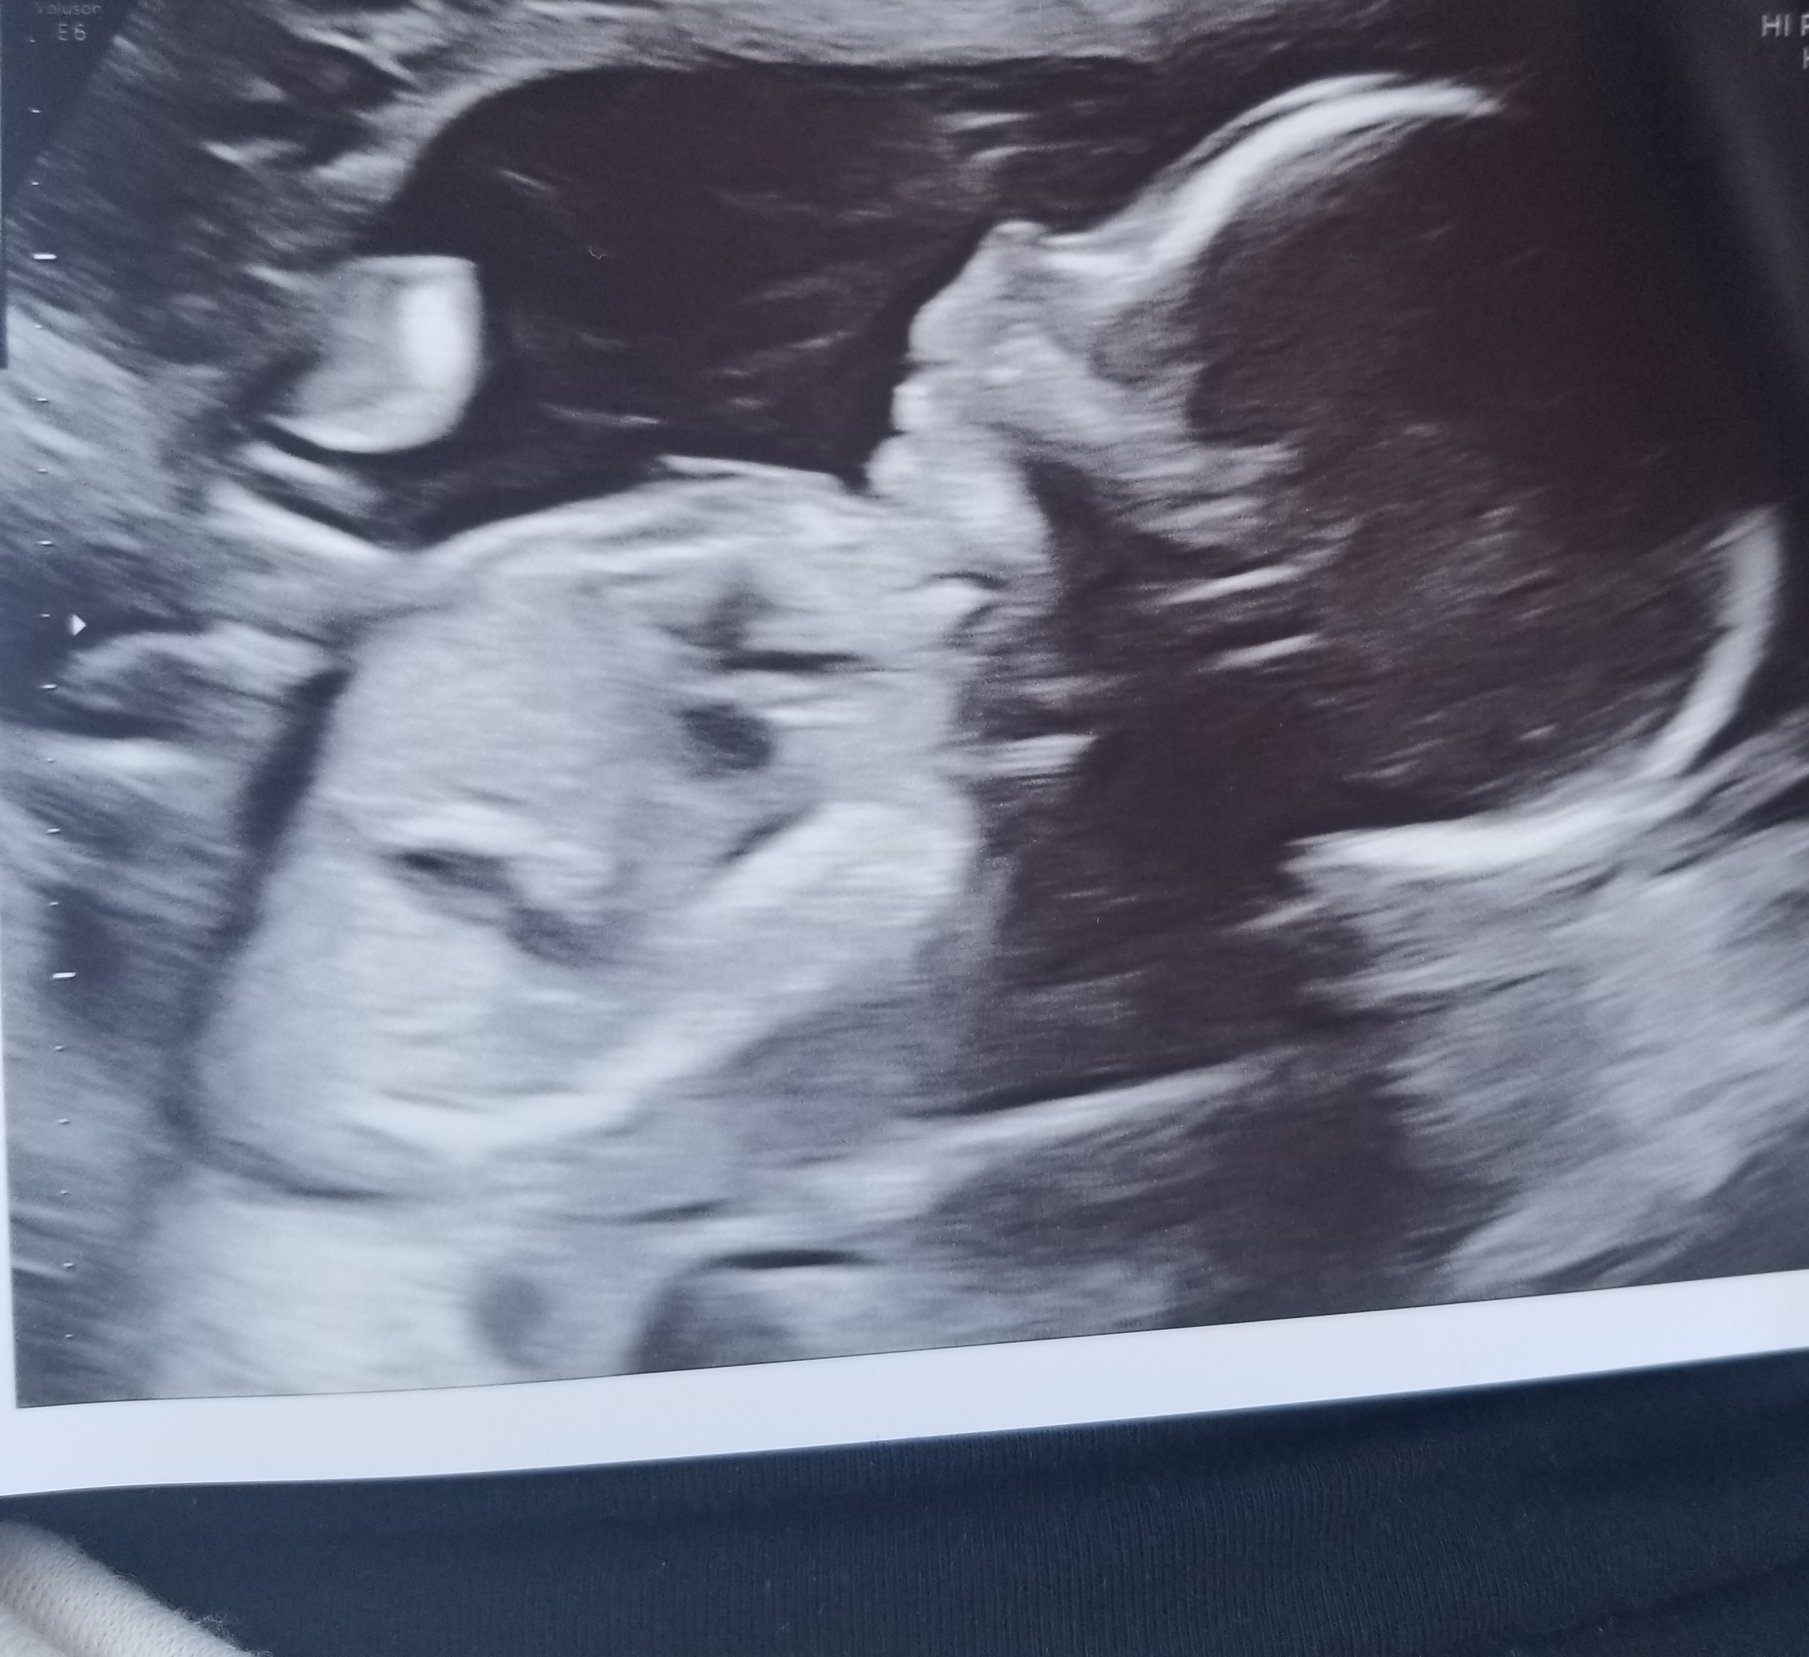

7/26/21 Ultrasound at 13 weeks 5 days. They say everything looks good. Baby has all it's limbs and organs. Super excited to find out the sex so I can start buying things and nervous for the NIPT results, but I'm always nervous about testing sooo......

7/26/21 Ultrasound at 13 weeks 5 days. They say everything looks good. Baby has all it's limbs and organs.

Super excited to find out the sex so I can start buying things and nervous for the NIPT results, but I'm always nervous about testing sooo......